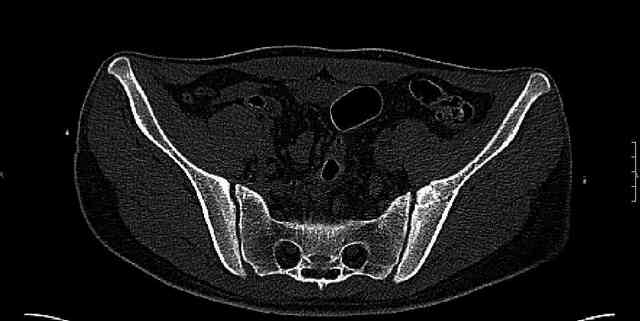

The last two images from the 3-D CT scan certainly makes the fracture look worse than the plan radiographs.

Might have to reconsider my suggestion to leave it alone at this stage.

Some more images. Does it help to guess which part of the acetabulum is displaced?

Normal appearing SI joints and a healed posterior column limb... my bet's on caudal segment displacement.